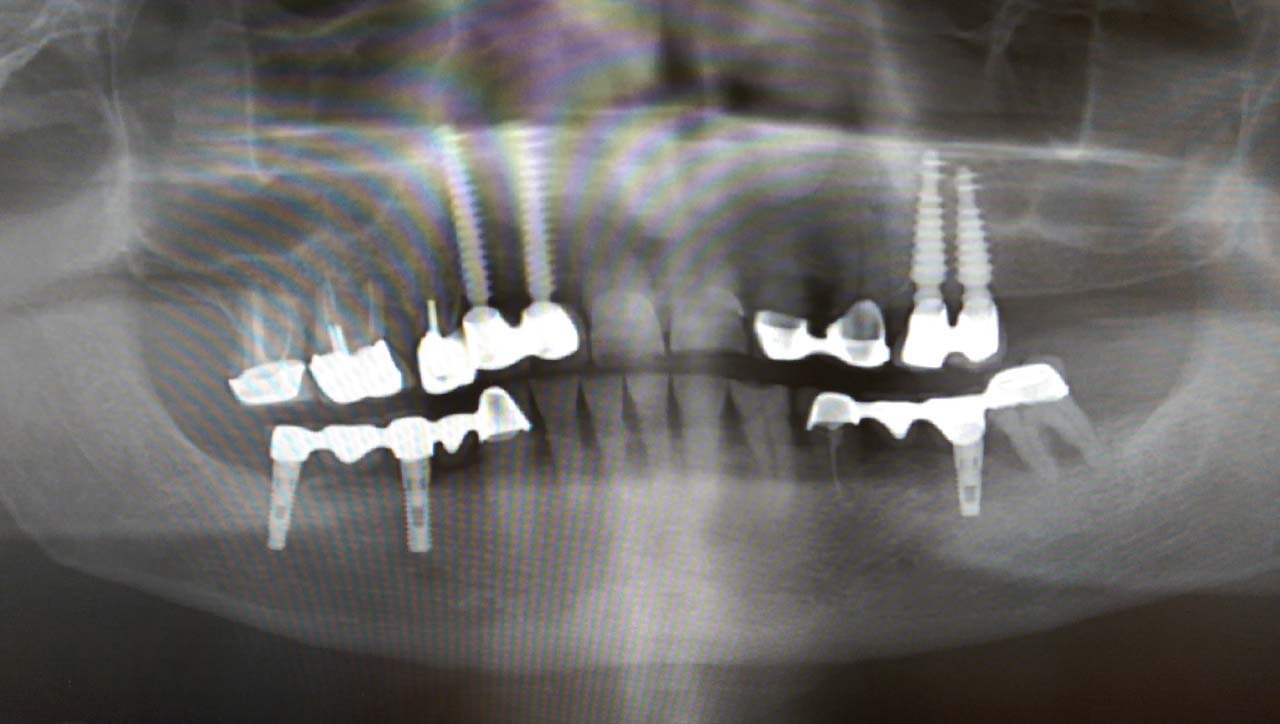

Teljes szájüregi rehabilitáció két lépésben

Ismét egy teljes szájüregi rehabilitáció két lépésben. Először az alsó fogak lettek kihúzva és azonnal implantálva, híddal ellátva, majd később a felső. IHDE svájci azonnal terhelhető implantátumok és cirkónium hidak. Dr. Kelemen Péter és a Symbion Fogtechnika közös munkája.